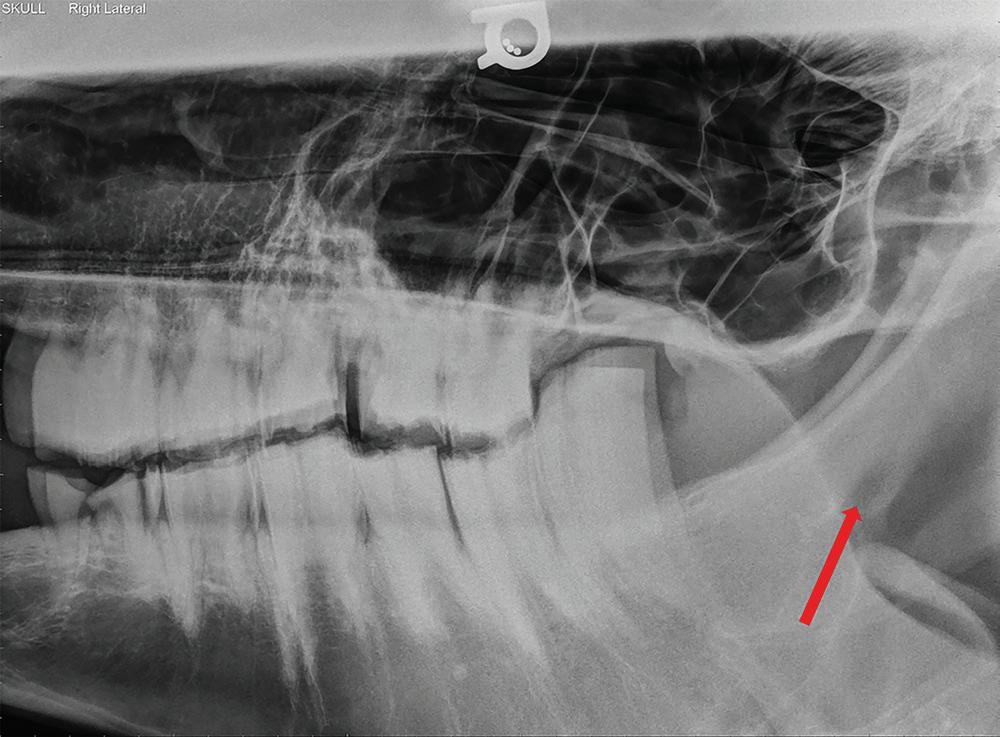

On endoscopy, narrowed nasal meati, purulent material, masses, or blood can be seen in

the nasal passage and/or draining from the sinus openings (Nickels 2012). Radiography of the skull may reveal free fluid lines, radiodense masses, paranasal sinus cysts, and lucency and/or proliferation associated with dental disease (Figure 1.1). Sinocentesis can be used to obtain fluid sample for culture and cytological examination. Sinuscopy with the horse standing and sedated is useful for the examination, diagnosis, and treatment of some disorders of the paranasal sinuses (Nickels 2012).

Figure 1.1 Lateral radiograph of a horse skull showing a fluid line (blue arrows) running through the caudal maxillary sinuses. The horse’s nose was angled downward resulting in the gravity-dependent fluid line being parallel to the ground. The sinusitis likely resulted from a periapical infection of a cheek tooth (red arrow). Maxillary nerve blockade can be used to desensitize the area for surgical removal of the tooth and drainage and lavage of the sinus.